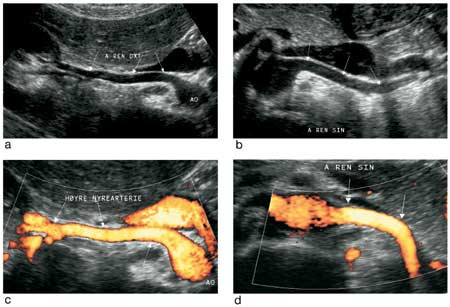

Med pasienten i ryggleie ble så aorta og nyrearterier undersøkt (fig 1). Etter vinkelkorreksjon ble det hentet ut dopplerkurver fra ulike avsnitt av arterien, særlig der det var påvist dopplerdistorsjon (aliasing). Hos alle overvektige har det vært forsøkt å fremstille nyrearteriene med gradert kompresjon og optimal innstilling for høy dopplersensitivitet. Målt maksimal systolisk hastighet (PSV) over 180 cm/s ble tolket som forenlig med signifikant stenose (fig 2). Det ble ikke brukt ultralydkontrastmiddel.